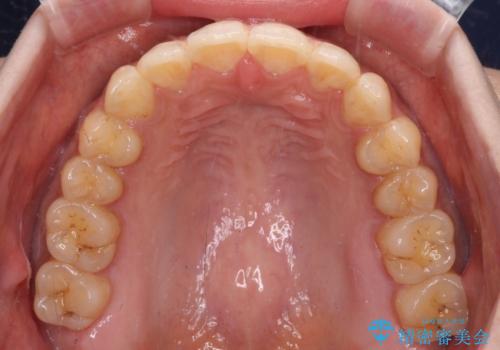

- 前歯のデコボコと上下前歯の隙間を気にして来院された患者様です。

下顎前歯はデコボコのため、歯肉が腫れやすくなっていました。

また、舌突出癖のため、上下前歯の間に隙間ができてしまい、上顎前歯が前方に傾斜している状態でした。

舌突出癖改善のためのトレーニングを行いながら、インビザラインにて矯正治療を行うこととしました。

舌のトレーニングをしっかりと行っていただき、上下前歯をしっかりと接触させることができました。

咬合力が強いため、治療途中に奥歯が咬み合わない期間が続きましたが、上下の奥歯でゴムかけを行っていただき、違和感なく咬み合うように仕上げることができました。